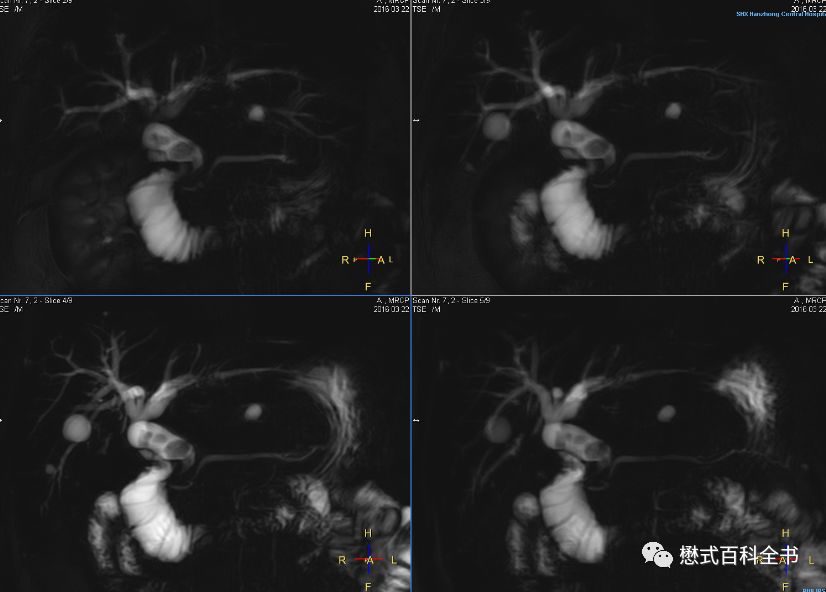

图14~16:扫描MRCP前注射6-542,十二指肠蠕动得到有效抑制,胆总管下段及十二指肠乳头部显示清楚(图片来源于陕西省汉中市中心医院培训)